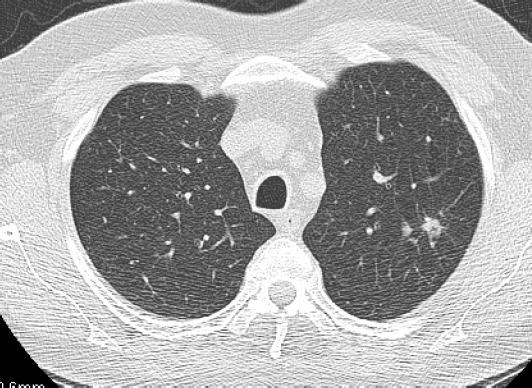

肺结节 “长个儿” 了?别慌!呼吸科医生教你科学应对 肺里的 “小疙瘩” 居然长个儿了?拿到体检报告的你是不是瞬间心跳加速?其实结节增大≠肺癌,就像脸上长痘痘,有的会自己消,有的要对症处理 —— 今天咱用大白话聊聊这事儿! 首先看 “增长成绩单”:3-6 个月内直径长了≥2mm,或体积涨了≥25%,才是真・增大。良性结节多是 “慢节奏”,比如炎症疤痕可能几年才长一点;恶性结节常是 “加速跑”,还可能悄悄变 “丑”。 再给结节 “颜值打分”:边缘光滑、圆滚滚的多是良性 “乖宝宝”;要是长了毛刺、分叶,或是拽着胸膜不放(胸膜牵拉),就得提高警惕。磨玻璃结节增大要留心,混杂密度结节若实性成分变多,建议尽快深入检查。 最后听 “专业会诊”:别自己瞎猜!医生会结合你的吸烟史、家族史,安排增强 CT “拍高清照”,必要时做穿刺活检 —— 这可是判断良恶性的 “金标准”。良性结节可能只需抗感染治疗或定期观察,就算是早期肺癌,微创手术治愈率超 90%,完全不用怕! 记住:结节增大是身体的 “提醒信号”,不是 “病危通知”。固定医院复查、保存好报告,跟着医生节奏来,就能守护肺部健康~ 毕竟,早发现早干预,肺结节也能 “变乖” 呀!